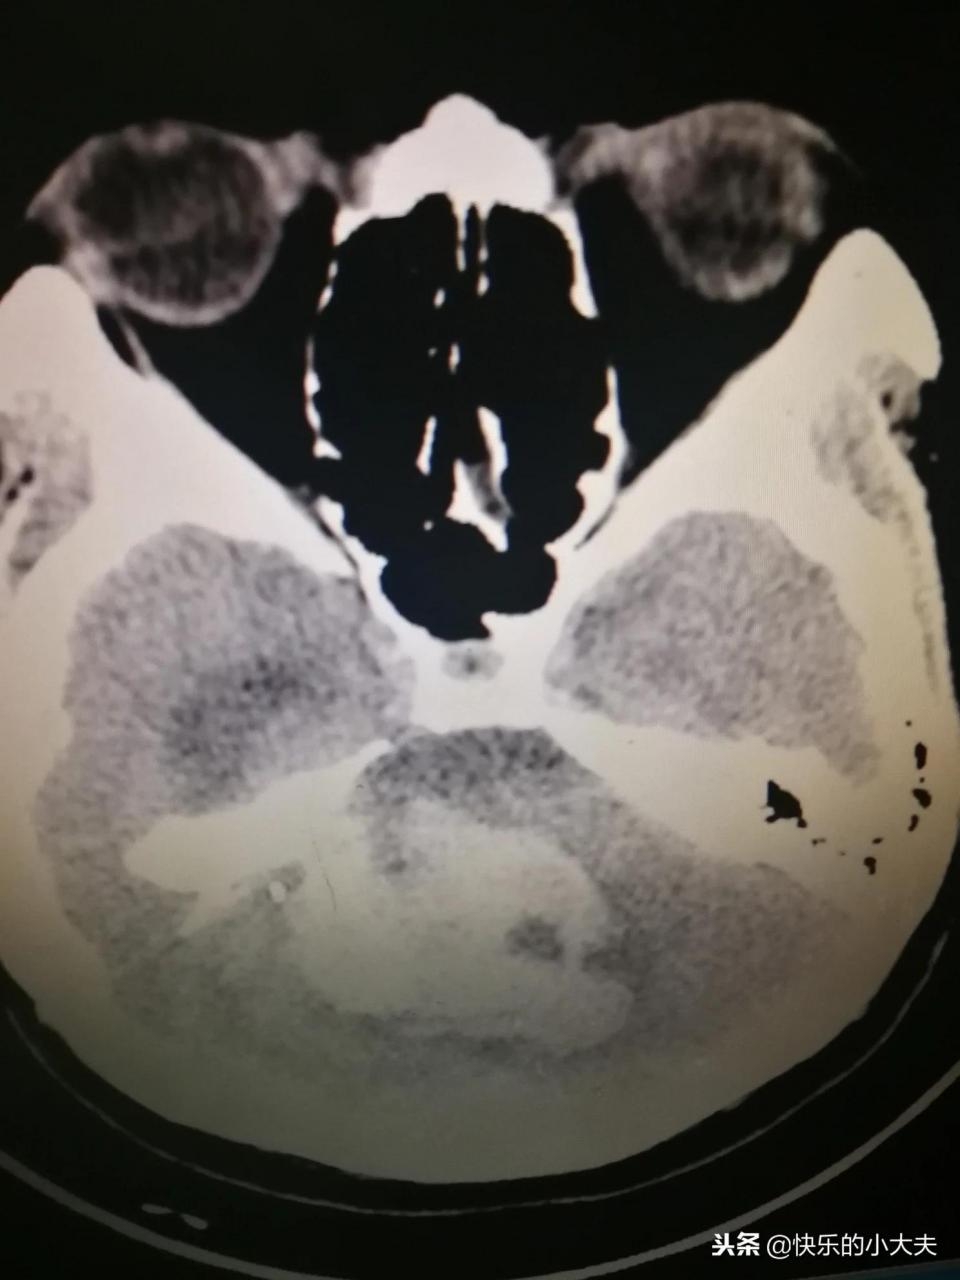

嚴重的腦出血

70歲患者突然昏迷,送到醫院后確診為腦出血,由于出血量大,部位關鍵,腦干也收到累及,考慮手術效果也不會太好。